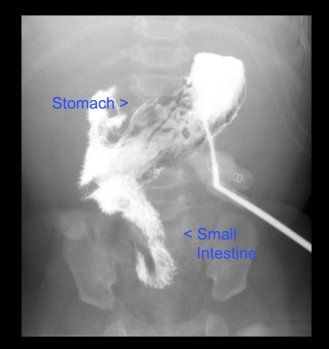

99106-fl-ugi

Transplant Pre-evaluation: Night 3 & Days 4 & 5